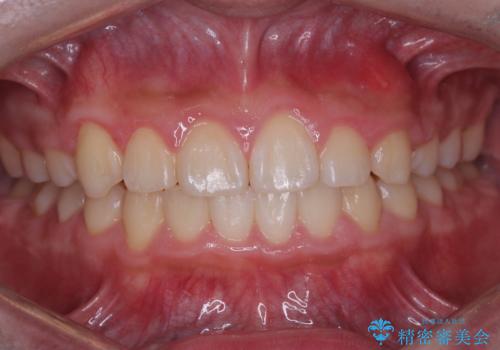

八重歯・歯並びのデコボコとディープバイトを改善した抜歯ワイヤー矯正症例

八重歯などの歯列のデコボコが綺麗に改善され、患者様にも大変喜んでいただけました。また、咬み合わせが深い「ディープバイト」も併せて改善し、見た目だけでなく機能面でもバランスの取れた咬合を獲得しています。